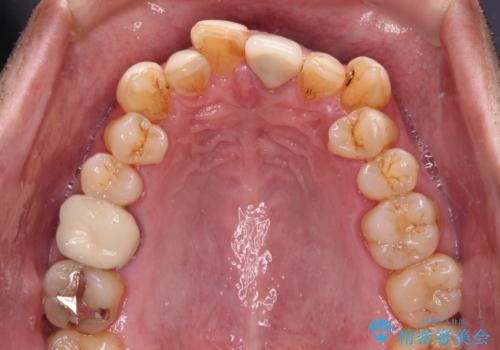

奥歯の銀歯は、土台の一部に抜歯が必要であったので、矯正治療の途中で抜歯してからオールセラミックブリッジによる補綴治療を行うこととしました。

外科処置は希望されなかったので、開咬の改善は限界があると事前にお話ししていたため、上下前歯が完全に接触する前に、もう十分改善したとのことで治療を終了しました。

インビザラインを毎日22時間しっかりと装着してくださったので、我々も驚愕するほどの治療成果が達成されました。